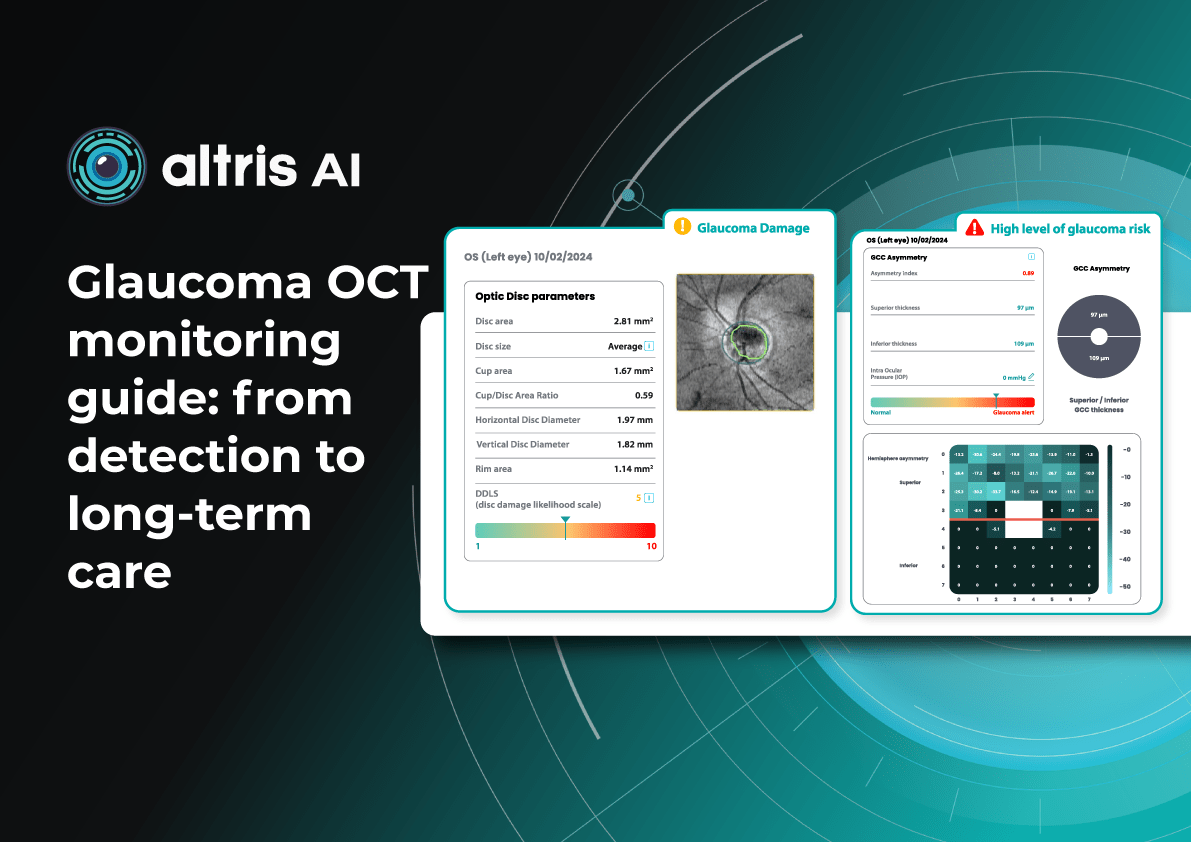

Her patients also appreciate Altris AI, which analyzes OCT scans for over 70 pathologies and biomarkers while also calculating the risk of developing glaucoma.

For instance, AI today can assess the early risk of glaucoma based on the GCC asymmetry measurements. Here is how AI-powered OCT workflow would look.

Altris AI, a leading AI software provider for OCT scan analysis, announces the appointment of Grant Schmid as the Vice President Business Development. Mr. Schmid is a proven leader in the eye care industry and has solid experience that will help him establish new partnerships for the company and lead corporate sales.

Altris AI is a part of the Altris Inc. ecosystem that includes Altris AI( a standalone AI platform for OCT scan analysis that improves diagnostic decision-making for eye care specialists) and Altris Education OCT (a free mobile app for OCT education interpretation). The mission of the company is to set higher diagnostic standards in the eye care industry and improve patient outcomes as a result. To achieve this mission the company created an AI-powered platform for OCT scan analysis that detects the biggest number of biomarkers and retina pathologies on the market today: 70 + including early glaucoma. More than that, the company offers an automated quantitative analysis of biomarkers and a progression analysis module for monitoring treatment results more efficiently.

Glaucoma risk evaluation

Millions risk irreversible vision loss due to undiagnosed glaucoma, underscoring the need for improved early detection. Current tests often rely on observing changes over time, delaying treatment assessment and hindering early identification of rapid disease progression. OCT frequently detects microscopic damage to ganglion cells and thinning across these layers before changes are noticeable through other tests. However, the earliest signs on the scan can still be invisible to the human eye.

AI algorithms offer insights into glaucoma detection by routinely analyzing the ganglion cell complex, measuring its thickness, and identifying any thinning or asymmetry to determine a patient’s glaucoma risk without additional clinician effort.

Another significant benefit of AI systems is that OCT for glaucoma usually utilizes a normative database to assess retinal normality. However, these databases are limited in size and represent an average of a select group of people, potentially missing early glaucoma development in those who deviate from the “norm.” Conversely, individuals may be unnecessarily referred for treatment due to not fitting the “normal” profile, even if their eyes are healthy.